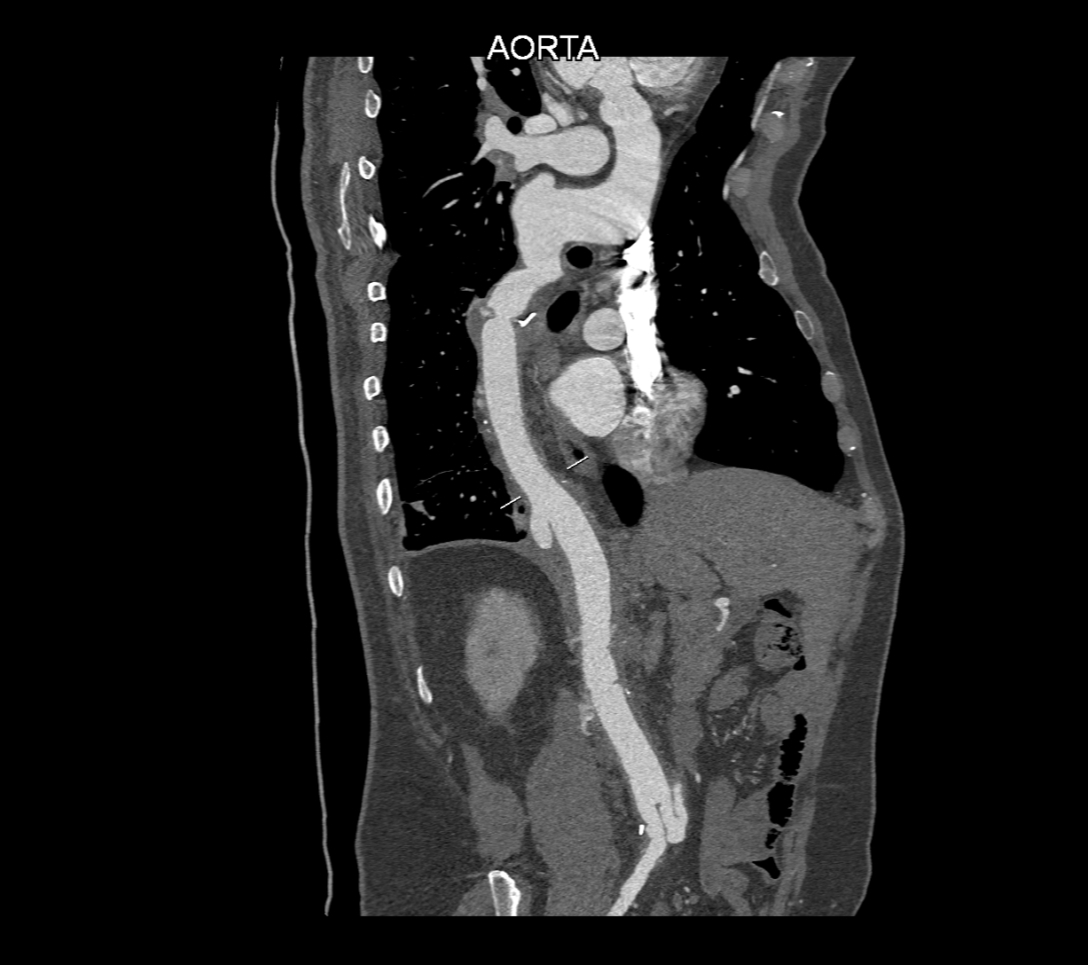

Figurile 2, 3 și 4: reconstrucţii oblic coronale aortă postoperator